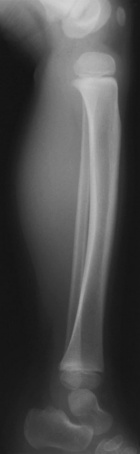

N.L. - 3 year old female with right calf mass; she denies any pain, her mother noticed it four weeks ago